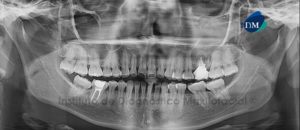

Paciente femenino de 34 años es referido al Instituto de Diagnóstico Maxilofacial para seguimiento de lesión en mandíbula. Se muestra la radiografía panorámica inicial (Figura